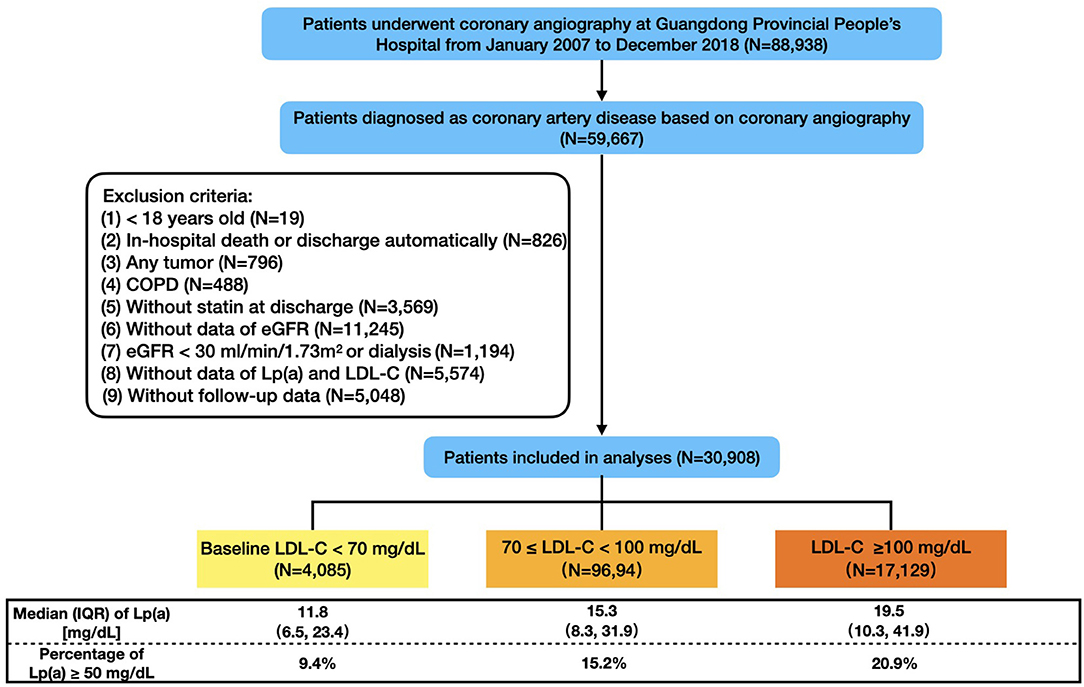

515hNQ8wKPL._BO30,255,255,, Frontiers | Baseline Low-Density-Lipoprotein Cholesterol,